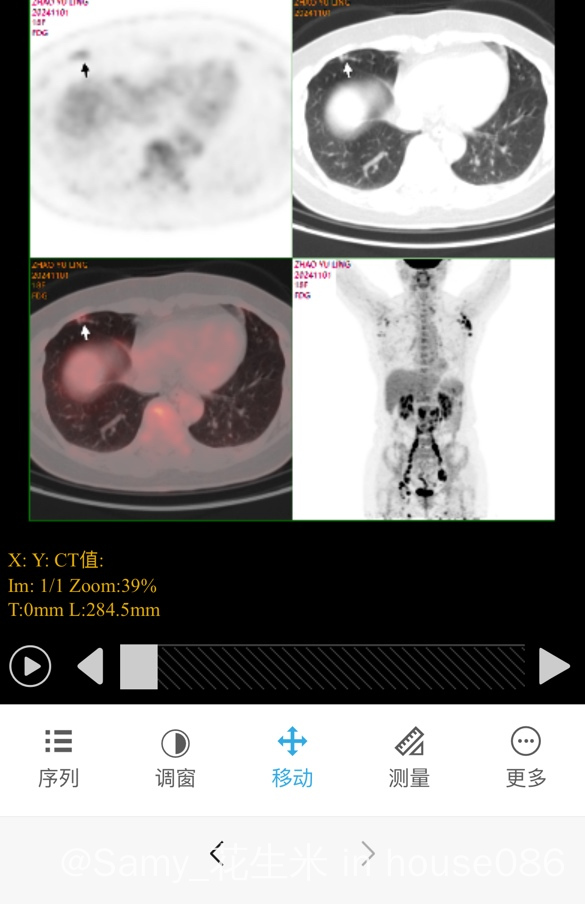

继免疫组化报告出来显示低级别滤泡淋巴瘤之后,基因检测也出来了。显示IG基因单克隆重拍。请问大神,IG单克隆重拍是什么意思?完全看不懂基因报告,感谢各位大神!@橙色雨丝 @常春藤2027